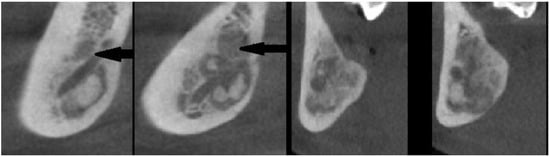

- various stages of calcifying masses inside of the lesion, Figure 5

- may cause cortical expansion or teeth displacement, Figure 5.